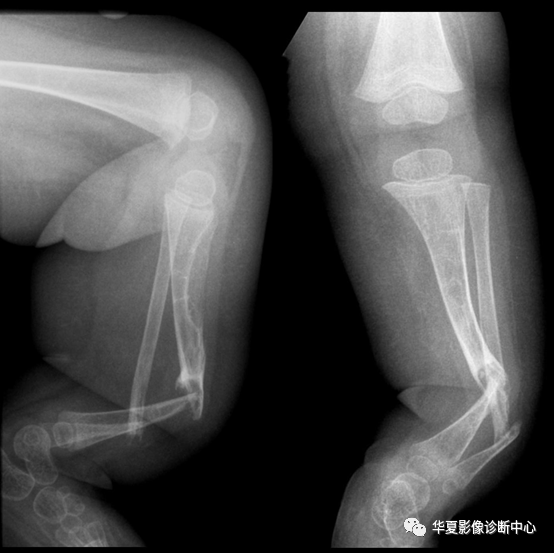

先天性胫骨假关节是病因尚不清楚的一种骨骼不连接的特殊类型的疾病,可在出生时或出生后而发生,先天性胫骨假关节最多见于胫骨中下1/3,有时同侧的腓骨也可发生假关节。

四、X线表现

(1)胫骨中下1/3交界处有假关节存在,假关节两端呈锥形,中间骨质吸收与消失,骨质细长,皮质板薄,腓骨有时出现同样改变。(2)胫骨中下1/3交界处有胫骨前弓,骨皮质增厚,骨髓腔纤维化,胫骨较短,髓腔内有囊性改变,腓骨可正常。(3)胫骨自后向外成角,较短,骨质变粗,髓腔可无变化。